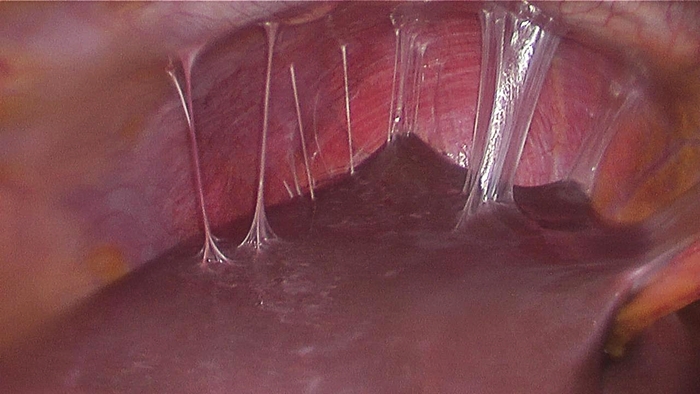

چسبندگی داخل رحمی یکی از علل شناخته شده ناباروری است. HSG و 2D SIS دو روش رایج برای تشخیص آن هستند، در حالی که هیسترئوسکوپی استاندارد طلایی است. نقش 3D USG در تشخیص به طور گسترده مورد بررسی قرار نگرفته است. یک مطالعه با مقایسه 3D USG و HSG گزارش داد که 3D USG دارای حساسیت 100٪ و HSG 66.7٪ برای تشخیص صحیح و درجه بندی چسبندگی های داخل رحمی است. HSG عمدتاً در تشخیص چسبندگی بخش تحتانی رحم شکست خورد و آنها را با انسداد کامل حفره اشتباه گرفت . احمدی تصدیق کرد که SIS سه بعدی ابزاری مفید و کم تهاجمی است.

هیستروسالپنگوگرافی سینکیا داخل رحمی

تعیین چسبندگی رحم

چسبندگی رحم که به عنوان سینکیای رحم نیز شناخته می شود، می تواند بر باروری تأثیر منفی بگذارد. سونوگرافی سه بعدی در شناسایی این چسبندگی ها نسبت به روش های سنتی مانند هیستروسالپنگوگرافی (فیلم رحمی دارویی) موثرتر است. با افزایش منطقه استفاده در سال های اخیر، بسیاری از ناهنجاری های رحم با سونوگرافی سه بعدی تشخیص داده می شوند.

چسبندگی داخل رحمی چیست؟

داخل رحم مثل یک بادکنک می باشد که دیواره های جلویی و پشتی رحم صاف بر روی یکدیگر قرار گرفته است. جیب با بافتی به نام آندومتر پوشیده شده است. در طی قاعدگی لایه سطحی (بالایی) آندومتر ریخته می شود. هنگامی که یک زن باردار می شود، جنین در آندومتر لانه گزینی می کند. آسیب به و/یا عفونت آندومتر ممکن است به پوشش داخلی رحم آسیب برساند و باعث ایجاد چسبندگی (بافت اسکار) بین دیوارههای داخلی رحم شود که در آن دیوارهها به طور غیر طبیعی به یکدیگر میچسبند یا میچسبند.

چگونه می توان چسبندگی رحم را تشخیص داد؟

چسبندگی رحم را می توان با هیستروسکوپی، هیستروسالپنگوگرام (HSG) یا سونوهیستروگرام سالین (SHG) تشخیص داد. HSG و SHG نیز تست های غربالگری مفیدی برای چسبندگی داخل رحمی هستند. HSG یک روش اشعه ایکس است که طی آن رنگی که در اشعه ایکس دیده می شود به داخل حفره رحم تزریق می شود تا شکل داخل رحم دیده شود. در طی سونوهیستروگرام سالین (SHG)، محلول آب نمکی مشابه مایع طبیعی بدن از طریق دهانه رحم به داخل رحم تزریق می شود و از دستگاه سونوگرافی برای دیدن حفره رحم استفاده می شود. در هر دو HSG و SHG، چسبندگی ها به عنوان "نقایص پر کردن" دیده می شوند، فضاهایی که مایع آزادانه در آن جریان ندارد. این روش های مطب نیازی به بیهوشی ندارند، اگرچه ممکن است از داروهای ضد التهابی غیر استروئیدی (NSAIDs) برای کاهش گرفتگی که ممکن است در طول عمل رخ دهد استفاده شود.

درمان جراحی چسبندگی داخل رحمی با هدایت هیستروسکوپی توصیه می شود. برای برش بافت اسکار از یک هیستروسکوپ ویژه عملیاتی استفاده می شود. این اغلب تحت بیهوشی انجام می شود، اما در برخی شرایط ممکن است در مطب پزشک انجام شود. پس از بریدن چسبندگی ها، بسیاری از جراحان توصیه می کنند که به طور موقت وسیله ای مانند کاتتر پلاستیکی یا بالون را در داخل رحم قرار دهند تا دیواره های رحم از هم دور بماند و احتمال اصلاح چسبندگی کاهش یابد. درمان هورمونی با استروژن و گاهی NSAID ها و/یا آنتی بیوتیک ها اغلب پس از جراحی تجویز می شود تا احتمال بازگشت چسبندگی ها کاهش یابد. در موارد شدید، ممکن است نیاز به بیش از یک عمل جراحی برای از بین بردن چسبندگی باشد و گاهی از هیستروسکوپی مطب به جای بالون برای کمک به حفظ حفره طبیعی استفاده می شود.